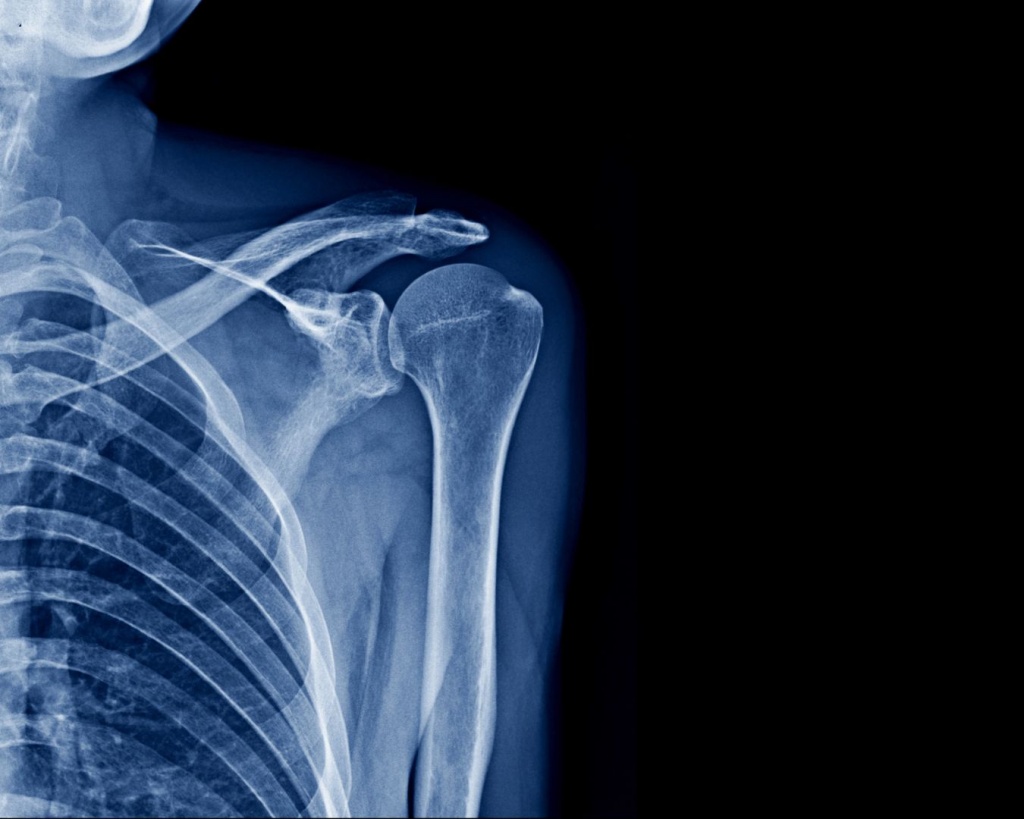

Плечовий суглоб – один із найбільш рухливих у тілі людини. Саме тому він особливо вразливий до травм, перевантажень і дегенеративних змін. Біль у плечі, скутість, хрускіт або зниження амплітуди рухів – це сигнали, які потребують чіткої та об’єктивної діагностики. Рентген плечового суглоба дозволяє швидко оцінити стан кісткових структур і визначити подальший план обстеження чи лікування.

Рентгенографія є базовим методом візуалізації, з якого починається діагностика більшості патологій плечового суглоба. Вона дає лікарю розуміння, чи є кісткові ушкодження, зміщення, ознаки запалення або хронічних змін.

На рентгенівських знімках оцінюють:

цілісність головки плечової кістки;

положення суглобових поверхонь;

наявність переломів і тріщин;

вивихи та підвивихи;

ознаки артрозу або посттравматичних змін;

деформації кісткових структур;

кальцифікації та кісткові розростання.

Знімки виконуються у стандартних і додаткових проєкціях, що дає змогу максимально точно оцінити анатомію плечового суглоба та уникнути пропущених ушкоджень.